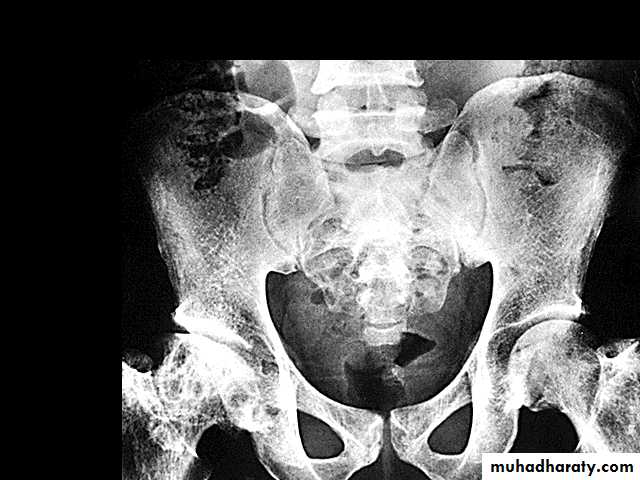

7.skeletal complication: - hand-foot syndrome. acute arthritis. aseptic necrosis. osteomyelitis . 8. Skin changes lead to chromic non- healing ulcer

ß- thalassemia major (ßoßo): is the most severe - Becomes apparent 3-6 months after birth when switch from Hb-F to Hb-A takes place :Hepatosplenomegaly(gall stones are also common )Expansion of the bones (hair on end appearance on skull X-ray examination).Severe anaemia with growth retardation and delayed sexual development Damage to heart, pancreas, endocrines and liver due to iron over load